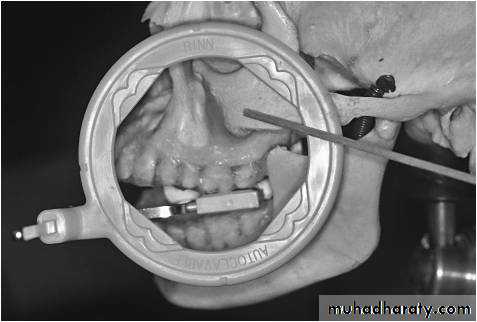

Coronoid process of the mandible may be imaged on intraoral radiographs of the maxillary posterior region. Note the position of the film holder when exposing a maxillary posterior periapical radiograph. The coronoid process of the mandible will most likely be imaged on this radiograph.

Radiographic Anatomy Basics